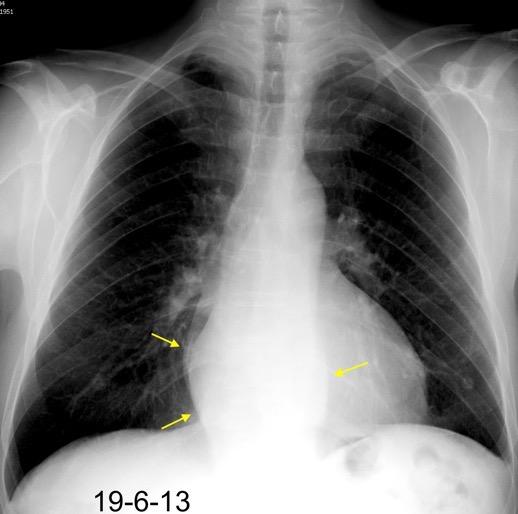

Ganglios retroperitoneales (flechas negras)

germinales del testículo izquierdo Nódulos pulmonares múltiples. (flechas verdes). Ganglios paratraqueales. (flechas amarillas). Dudoso ensanchamiento retrocrural (flechas negras)

Panda A et al. “Straddling Across Boundaries”. Thoracoabdominal Lesions: Spectrum and Pattern Approach. Curr Probl Diagn Radiol, 2015